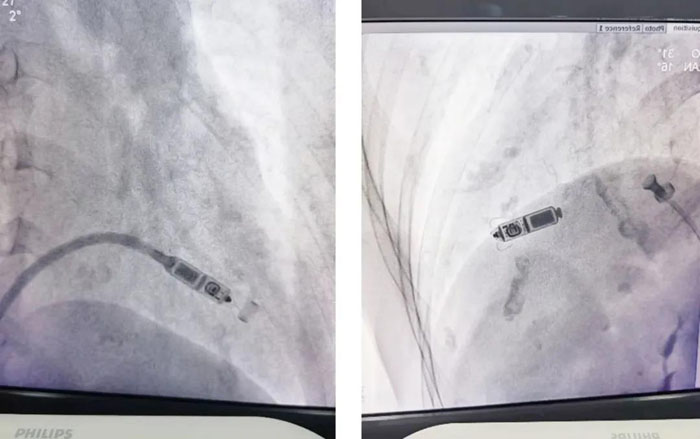

本次手術(shù)在北京專家的指導(dǎo)下,由CCU電生理醫(yī)師協(xié)作將“膠囊”起搏器精準地定位于心室中間隔的右隔面,造影確定后快速釋放,測定參數(shù)良好,并放大X線影像進行牽拉試驗,確認起搏器的四個爪中有三個已刺入間隔心肌中(有兩個爪刺入心肌即符合要求),一次性操作成功,復(fù)查心電圖進一步證實了起搏位點位于中間隔,45分鐘完成該項手術(shù),縫合壓迫止血后,患者安返病房。??